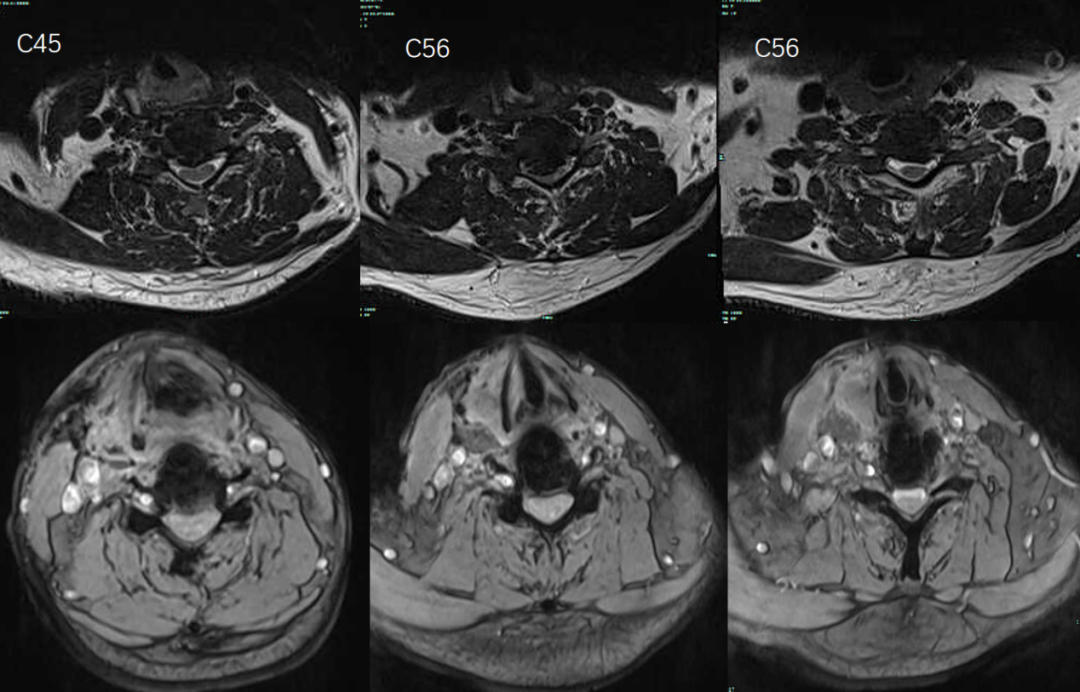

术前术后MRI: